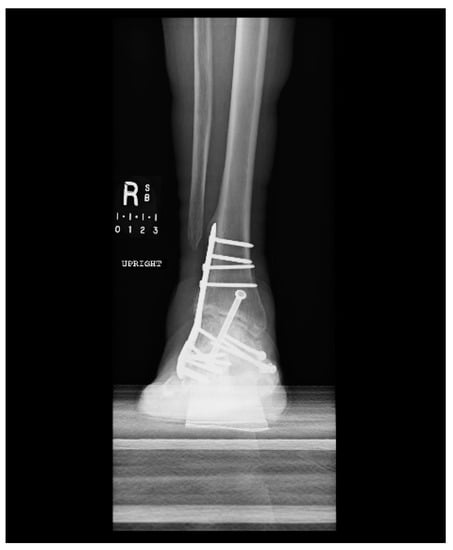

1.1.4. Post-Operative Imaging